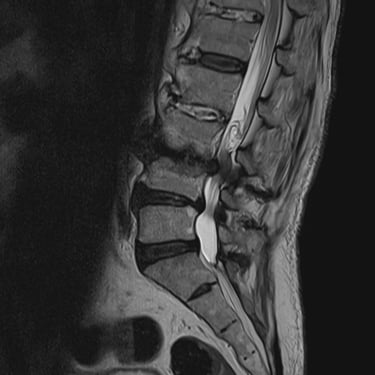

🧠 Hernia Lumbar L5–S1 Derecha: Alivio del Dolor con Microdiscectomía.

La hernia lumbar L5–S1 derecha provoca dolor lumbar y radicular persistente. La microdiscectomía permite descomprimir el nervio afectado mediante una técnica precisa y mínimamente invasiva, logrando alivio del dolor, mejoría funcional y una recuperación más rápida.